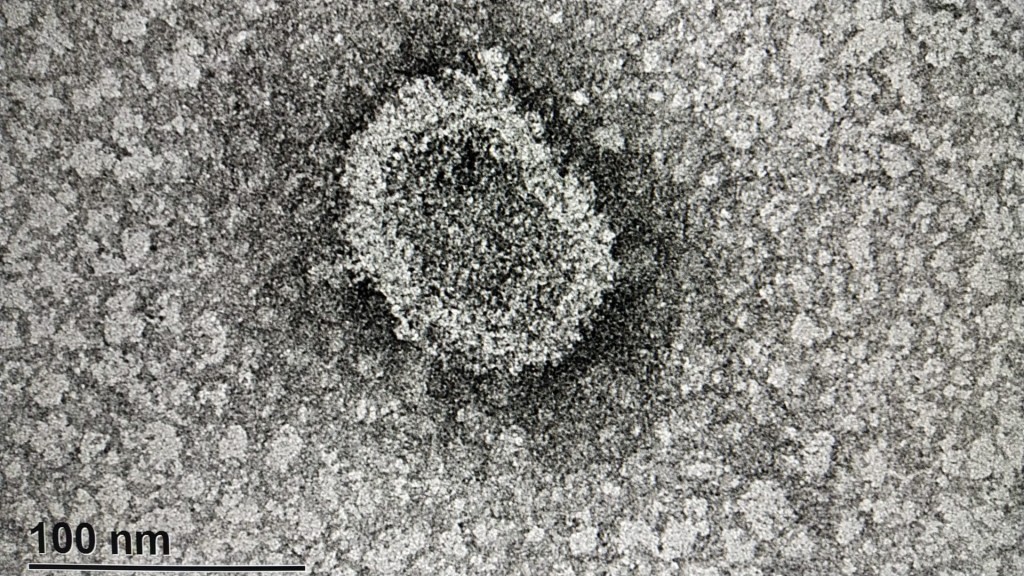

En el CURE Rocha lograron las primeras imágenes del Coronavirus tomadas en Uruguay

Así lo informó a través de su cuenta de Twitter el Rector de la UDELAR, Rodrigo Arim: "fueron capturadas con el microscopio electrónico de la sede Rocha del CURE- UdelaR por parte del profesor Alvaro Olivera, licenciado en Bioquímica, a partir de muestras enviadas por el laboratorio de virología del Centro Universitario Litoral Norte. La muestra había sido extraída por la profesora Viviana Bortagaray del laboratorio de virología, sede Salto del Centro Universitario Regional Litoral Norte.